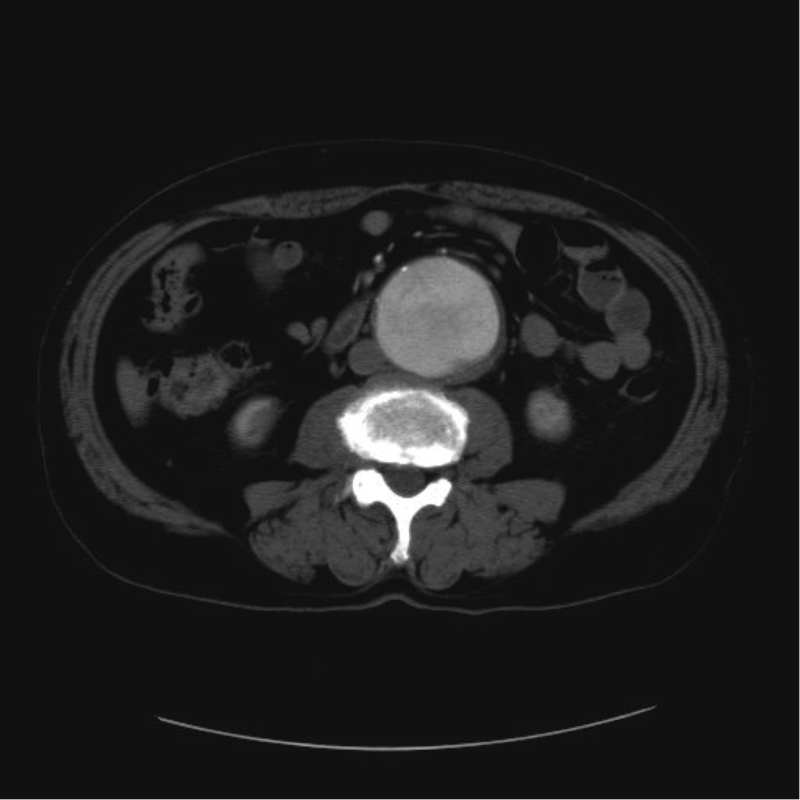

大動脈とは、体のなかでもっとも太い血管であり、全身に血液を送り出す動脈の幹です。お腹に位置する大動脈の直径は通常2㎝ほどです。その大動脈の一部が直径3㎝以上の瘤状に膨れたものを、腹部大動脈瘤といいます。腹部大動脈瘤の多くは、腎動脈*よりも下の位置に発生します。

先に述べたように、破裂していない腹部大動脈瘤の場合、患者さんの自覚症状はほぼありません。そのため、腹部大動脈瘤は、違う病気を調べるための超音波検査やCT*検査、MRI*検査、もしくは健康診断や人間ドックなどでみつかることが多いです。たとえば、心臓の超音波検査を受けた際や整形外科でMRI検査を受けた際などに腹部大動脈瘤がみつかり、当院を訪れる患者さんもいらっしゃいます。

CT検査…エックス線を使って身体の断面を撮影する検査。